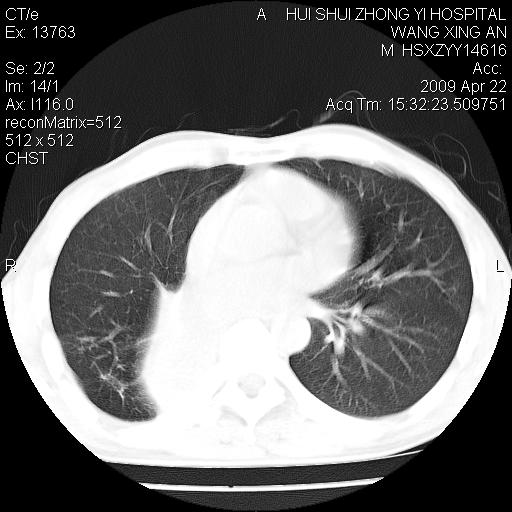

标题: CT19534:患者男、46岁咳嗽、胸痛半月。 [打印本页]

标题: CT19534:患者男、46岁咳嗽、胸痛半月。

考虑---右肺中心型肺癌继发下叶不张,少量胸水。

支持右侧中央型肺ca并右下肺不张、右侧胸腔少量积液。

1、右下肺中央型肺癌并右肺转移,右肺下叶不张。(右肺有结节影)。

2、右中上肺陈旧性肺结核(因为大多为纤维灶)。

3、右侧胸腔积液。

1、右下肺中央型肺癌并右肺转移,右肺下叶不张。(肿块围绕右肺下叶支气管生长,致管腔闭塞右肺下叶不张;右肺有结节影)。

2、右侧胸腔积液。

3、右中上肺陈旧性肺结核(右肺见纤维化病灶及点状钙化)。